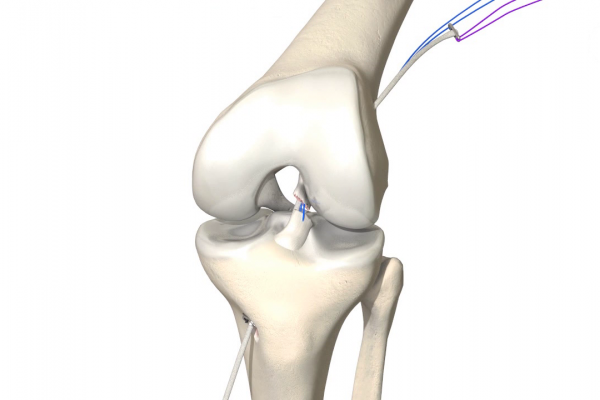

Ist das Kreuzband vollständig abgerissen ist eine Heilung ohne Operation nicht möglich. Um das Kreuzband dennoch zu erhalten kommt die Ligamys® Technik oder „Dynamische Intraligamentäre Stabilisierung“ zum Einsatz. Hierbei wird das abgerissene Kreuzband über eine wenig Millimeter messende Bohrung mit Nähten wieder am Oberschenkelknochen fixiert. Um die Naht in der Zeit der Heilung zu schützen wird eine stabile Kordel als innere Schienung parallel zum Kreuzband gespannt. Diese Kordel wird im Unterschenkelknochen im eigentlichen Ligamys® Implantat verankert. Hier sorgt eine Feder dafür, dass die Kordel über das gesamte Bewegungsausmaß die selbe Spannung behält. Der gesamte Eingriff wird im Rahmen einer Kniegelenksspiegelung also ohne weite Eröffnung des Kniegelenks durchgeführt.

Die entnommene Sehne wird mehrfach gefaltet und mit sich selbst vernäht. Zur Fixierung werden Knochenkanäle in den Unterschenkel und Oberschenkelknochen gebohrt. Hierbei ist die Kenntnis der genauen Ansatzpunkte des vorderen Kreuzbandes von entscheidender Bedeutung für ein optimales Operationsergebnis. Die Sehne wird im Rahmen der Kniegelenksspiegelung in die Knochentunnel eingezogen und mittels Titanankern bzw. sich selbst auflösenden Schrauben fixiert.